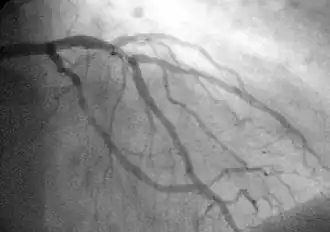

Coronary catheterization is one of the several cardiology diagnostic tests and procedures. Specifically, through the injection of a liquid radiocontrast agent and illumination with X-rays,[1] angiocardiography allows the recognition of occlusion, stenosis, restenosis, thrombosis or aneurysmal enlargement of the coronary artery lumens; heart chamber size; heart muscle contraction performance; and some aspects of heart valve function. Important internal heart and lung blood pressures, not measurable from outside the body, can be accurately measured during the test. The relevant problems that the test deals with most commonly occur as a result of advanced atherosclerosis – atheroma activity within the wall of the coronary arteries. Less frequently, valvular, heart muscle, or arrhythmia issues are the primary focus of the test.

The catheter is itself designed to be radiodense for visibility and it allows a clear, watery, blood compatible radiocontrast agent, commonly called an X-ray dye, to be selectively injected and mixed with the blood flowing within the artery. Typically 3–8 cc of the radiocontrast agent is injected for each image to make the blood flow visible for about 3–5 seconds as the radiocontrast agent is rapidly washed away into the coronary capillaries and then coronary veins. Without the X-ray dye injection, the blood and surrounding heart tissues appear, on X-ray, as only a mildly-shape-changing, otherwise uniform water density mass; no details of the blood and internal organ structure are discernible. The radiocontrast within the blood allows visualization of the blood flow within the arteries or heart chambers, depending on where it is injected.

If atheroma, or clots, are protruding into the lumen, producing narrowing, the narrowing may be seen instead as increased haziness within the X-ray shadow images of the blood/dye column within that portion of the artery; this is as compared to adjacent, presumed healthier, less stenotic areas.